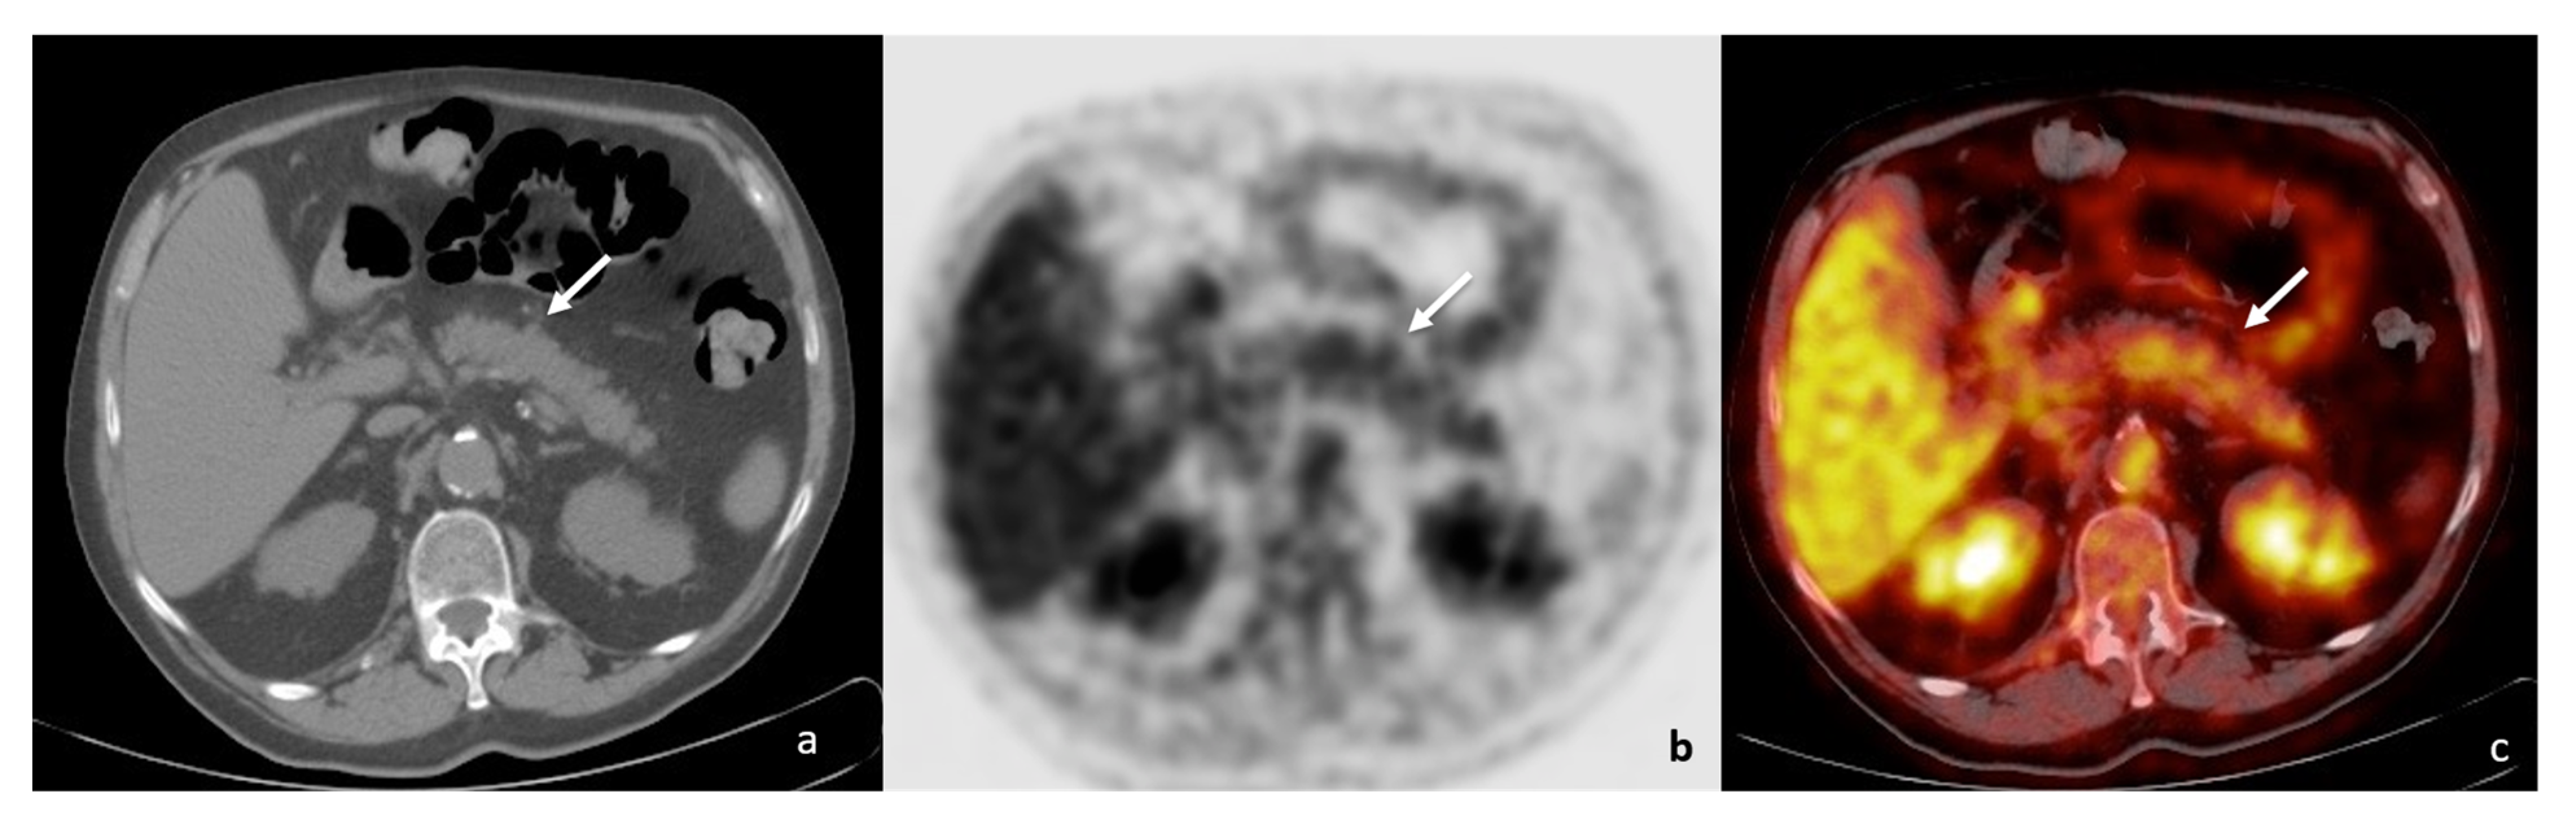

- Zhang, J.; Jia, G.; Zuo, C.; Jia, N.; Wang, H. 18F- FDG PET/CT helps differentiate autoimmune pancreatitis from pancreatic cancer. BMC Cancer 2017, 17, 695. [Google Scholar] [CrossRef]

- Sun, G.-F.; Zuo, C.-J.; Shao, C.-W.; Wang, J.-H.; Zhang, J. Focal autoimmune pancreatitis: Radiological characteristics help to distinguish from pancreatic cancer. World J. Gastroenterol. 2013, 19, 3634–3641. [Google Scholar] [CrossRef]

- Vijayakumar, A.; Vijayakumar, A. Imaging of focal autoimmune pancreatitis and differentiating it from pancreatic cancer. ISRN Radiol. 2013, 2013, 569489. [Google Scholar] [CrossRef]

- Schima, W.; Böhm, G.; Rösch, C.S.; Klaus, A.; Függer, R.; Kopf, H. Mass-forming pancreatitis versus pancreatic ductal adenocarcinoma: CT and MR imaging for differentiation. Cancer Imaging 2020, 20, 52. [Google Scholar] [CrossRef]

- Lee, T.Y.; Kim, M.-H.; Park, D.H.; Seo, D.W.; Lee, S.K.; Kim, J.S.; Lee, K.T. Utility of 18F-FDG PET/CT for Differentiation of Autoimmune Pancreatitis with Atypical Pancreatic Imaging Findings From Pancreatic Cancer. Am. J. Roentgenol. 2009, 193, 343–348. [Google Scholar] [CrossRef]

- Das, J.P.; Halpenny, D.; Do, R.K.; Ulaner, G.A. Focal Immunotherapy-Induced Pancreatitis Mimicking Metastasis on FDG PET/CT. Clin. Nucl. Med. 2019, 44, 836–837. [Google Scholar] [CrossRef]

- Huang, S.; Chong, H.; Sun, X.; Wu, Z.; Jia, Q.; Zhang, Y.; Lan, X. The Value of 18F-FDG PET/CT in Diagnosing Pancreatic Lesions: Comparison with CA19-9, Enhanced CT or Enhanced MR. Front. Med. 2021, 8, 668697. [Google Scholar] [CrossRef]